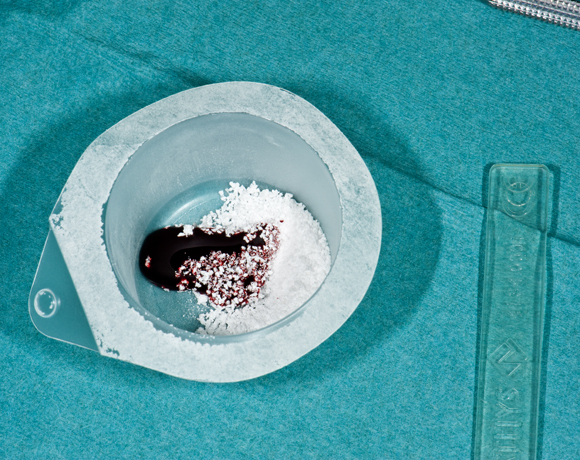

Bild 05 – 09: CEROS® TCP PUTTY